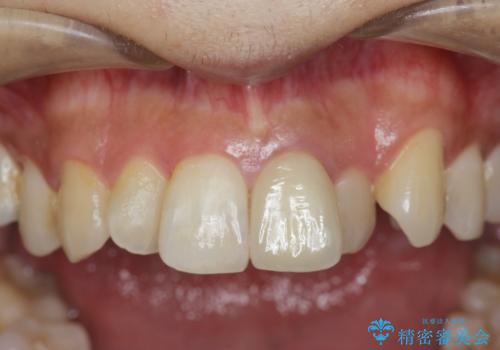

歯の変色 前歯の審美改善